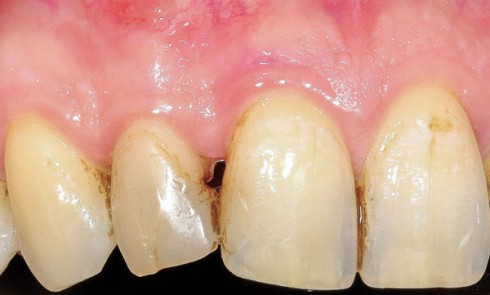

Article réservé à nos abonnés Le collage à la dentine sclérotique

Différences entre la dentine saine et sclérotique La dentine « saine » est composée d’une partie minérale (47 % du volume), d’une partie...